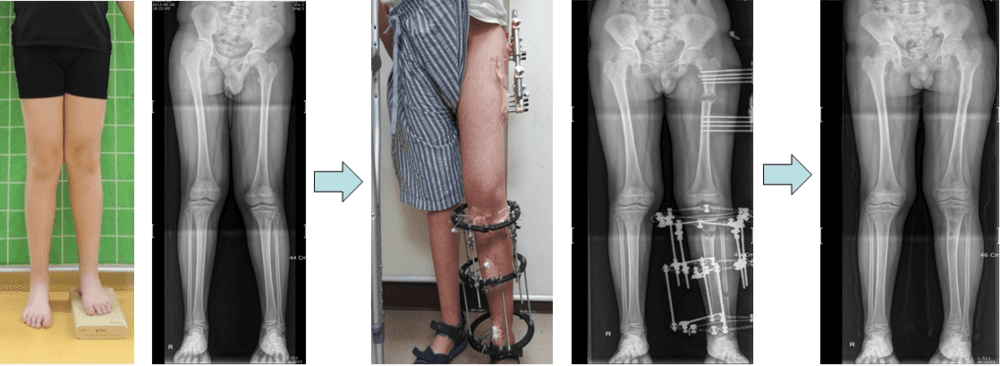

Lower Limb Lengthening in Short Stature